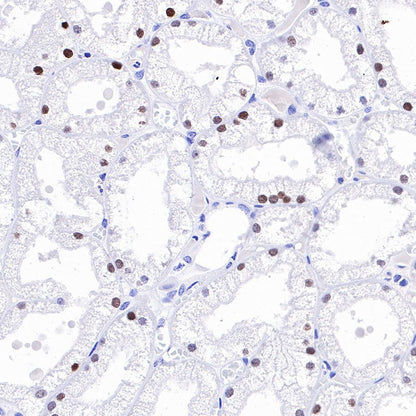

IHC shows positive staining in paraffin-embedded human kidney. Anti-HNF4α antibody was used at 1/500 dilution, followed by a HRP Polymer for Mouse & Rabbit IgG (ready to use). Counterstained with hematoxylin. Heat mediated antigen retrieval with Tris/EDTA buffer pH9.0 was performed before commencing with IHC staining protocol.

IHC shows positive staining in paraffin-embedded rat kidney. Anti-HNF4α antibody was used at 1/500 dilution, followed by a HRP Polymer for Mouse & Rabbit IgG (ready to use). Counterstained with hematoxylin. Heat mediated antigen retrieval with Tris/EDTA buffer pH9.0 was performed before commencing with IHC staining protocol.